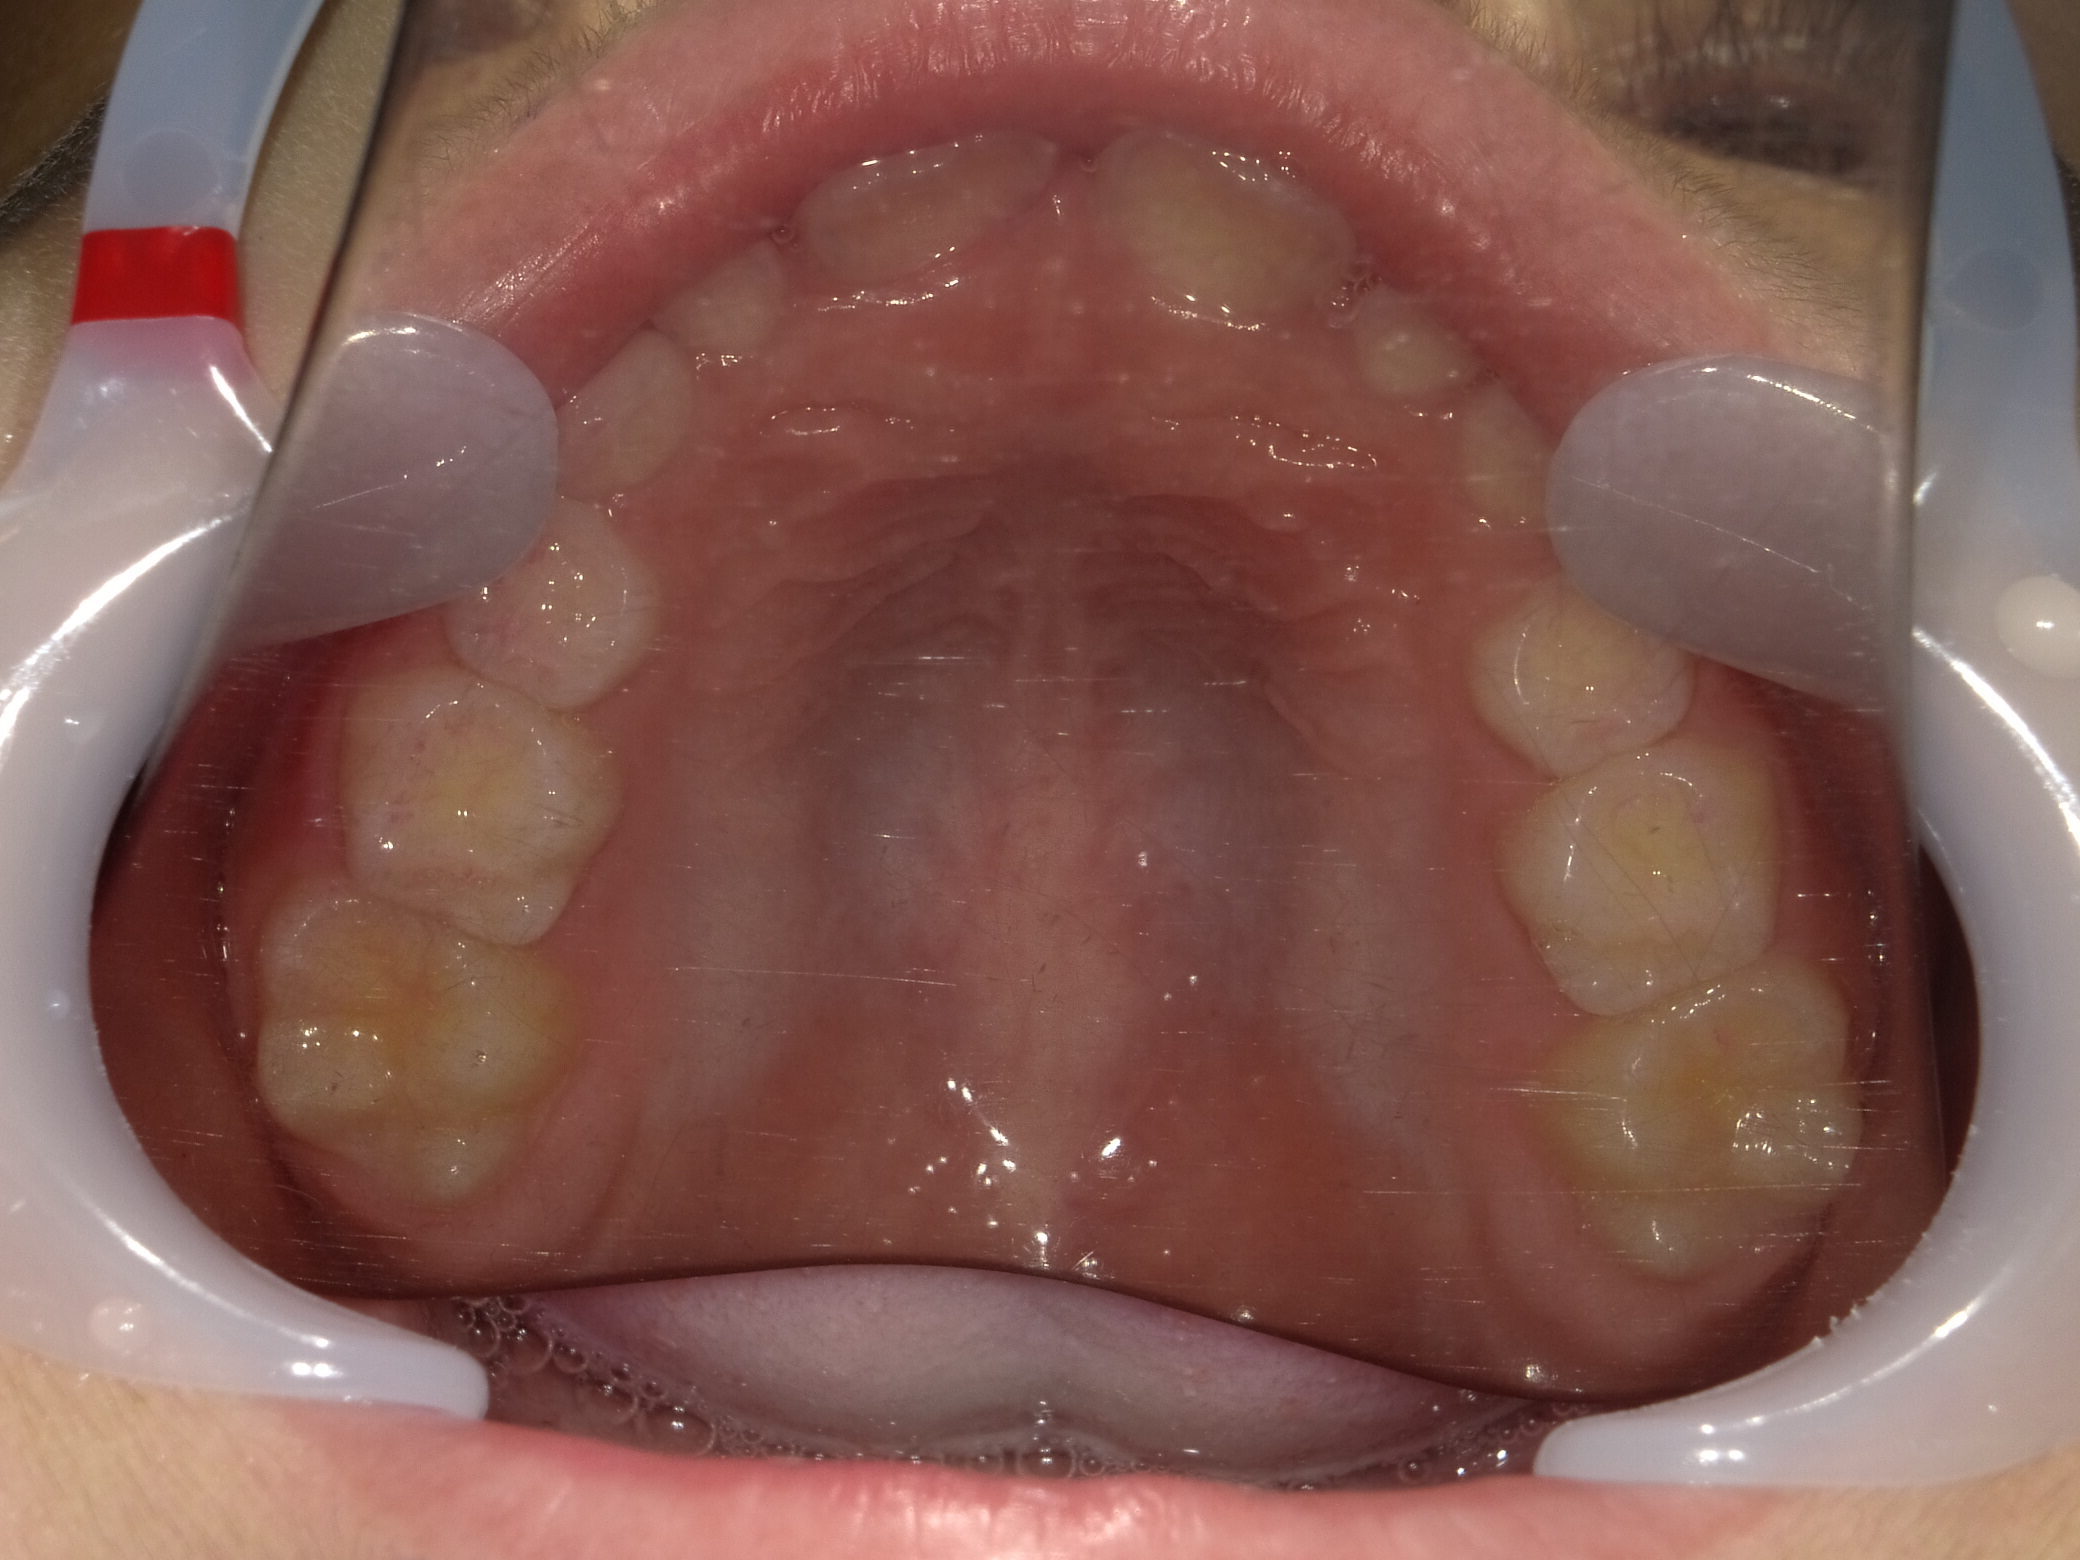

上顎